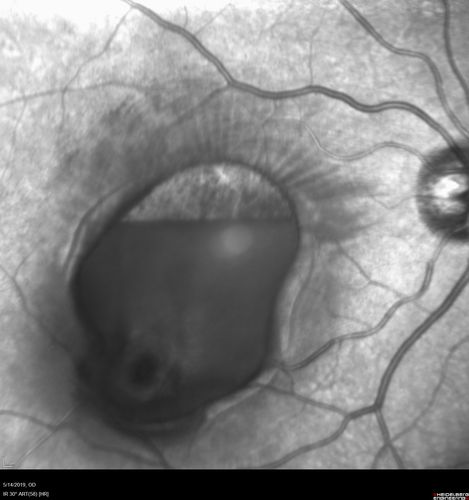

Macroaneurysm - Macular Hemorrhage - Branch Retinal Aterial Occlusion

62 year old African American female with chronic hypertension and vision loss for 2 weeks. VA is 20/400

Macroaneurym - Fresh Macular Hemorrhage - branch retinal arterial occulsion distal to MA